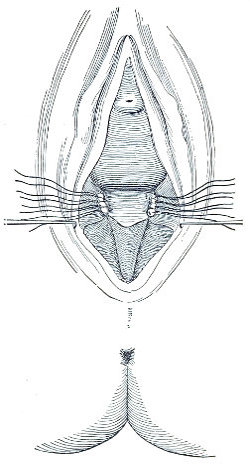

Slight Median laceration of the Perineum.—In this injury the tear takes place through the fourchette. Posteriorly it may extend as far as the sphincter ani muscle. Upward it may extend for an inch up the posterior vaginal wall. The appearance of this tear is shown in Fig. 33. It will be noted that, as this tear takes place in the median line, none of the muscles that support the perineum are involved, nor are the planes of fascia injured. The perineum is slightly split, and the insertions and origins of the muscles and the fascia are slightly separated. The supporting structures of the perineum and the pelvic floor are, however, uninjured.

Fig. 33.—Recent slight median laceration of the perineum: sutures introduced.

If this tear is detected after labor, it should be closed by the immediate operation. A slight tear involving chiefly the cutaneous aspect of the perineum should be closed by three or four sutures introduced from the outside, as in Fig. 33. The needle should be introduced about a quarter of an inch from the edge of the wound. It should not be passed parallel with the plane of the lacerated surface, but should be swept outward and then inward toward the 68 angle at the bottom of the tear (Fig. 34). It may either emerge at the angle and be re-introduced, or it may be passed directly through to the skin-margin on the opposite side of the wound. If the suture is passed in this way, there will be perfect apposition throughout the whole surface of laceration. If the sutures are improperly passed, there may result only apposition of the skin-edges.

Fig. 34.—Diagram representing the correct and the incorrect method of passing the suture for closure of slight perineal laceration.

If the laceration extends up the posterior vaginal wall, two sets of sutures must be introduced—one on the vaginal aspect of the tear, and one on the skin aspect (Fig. 35).